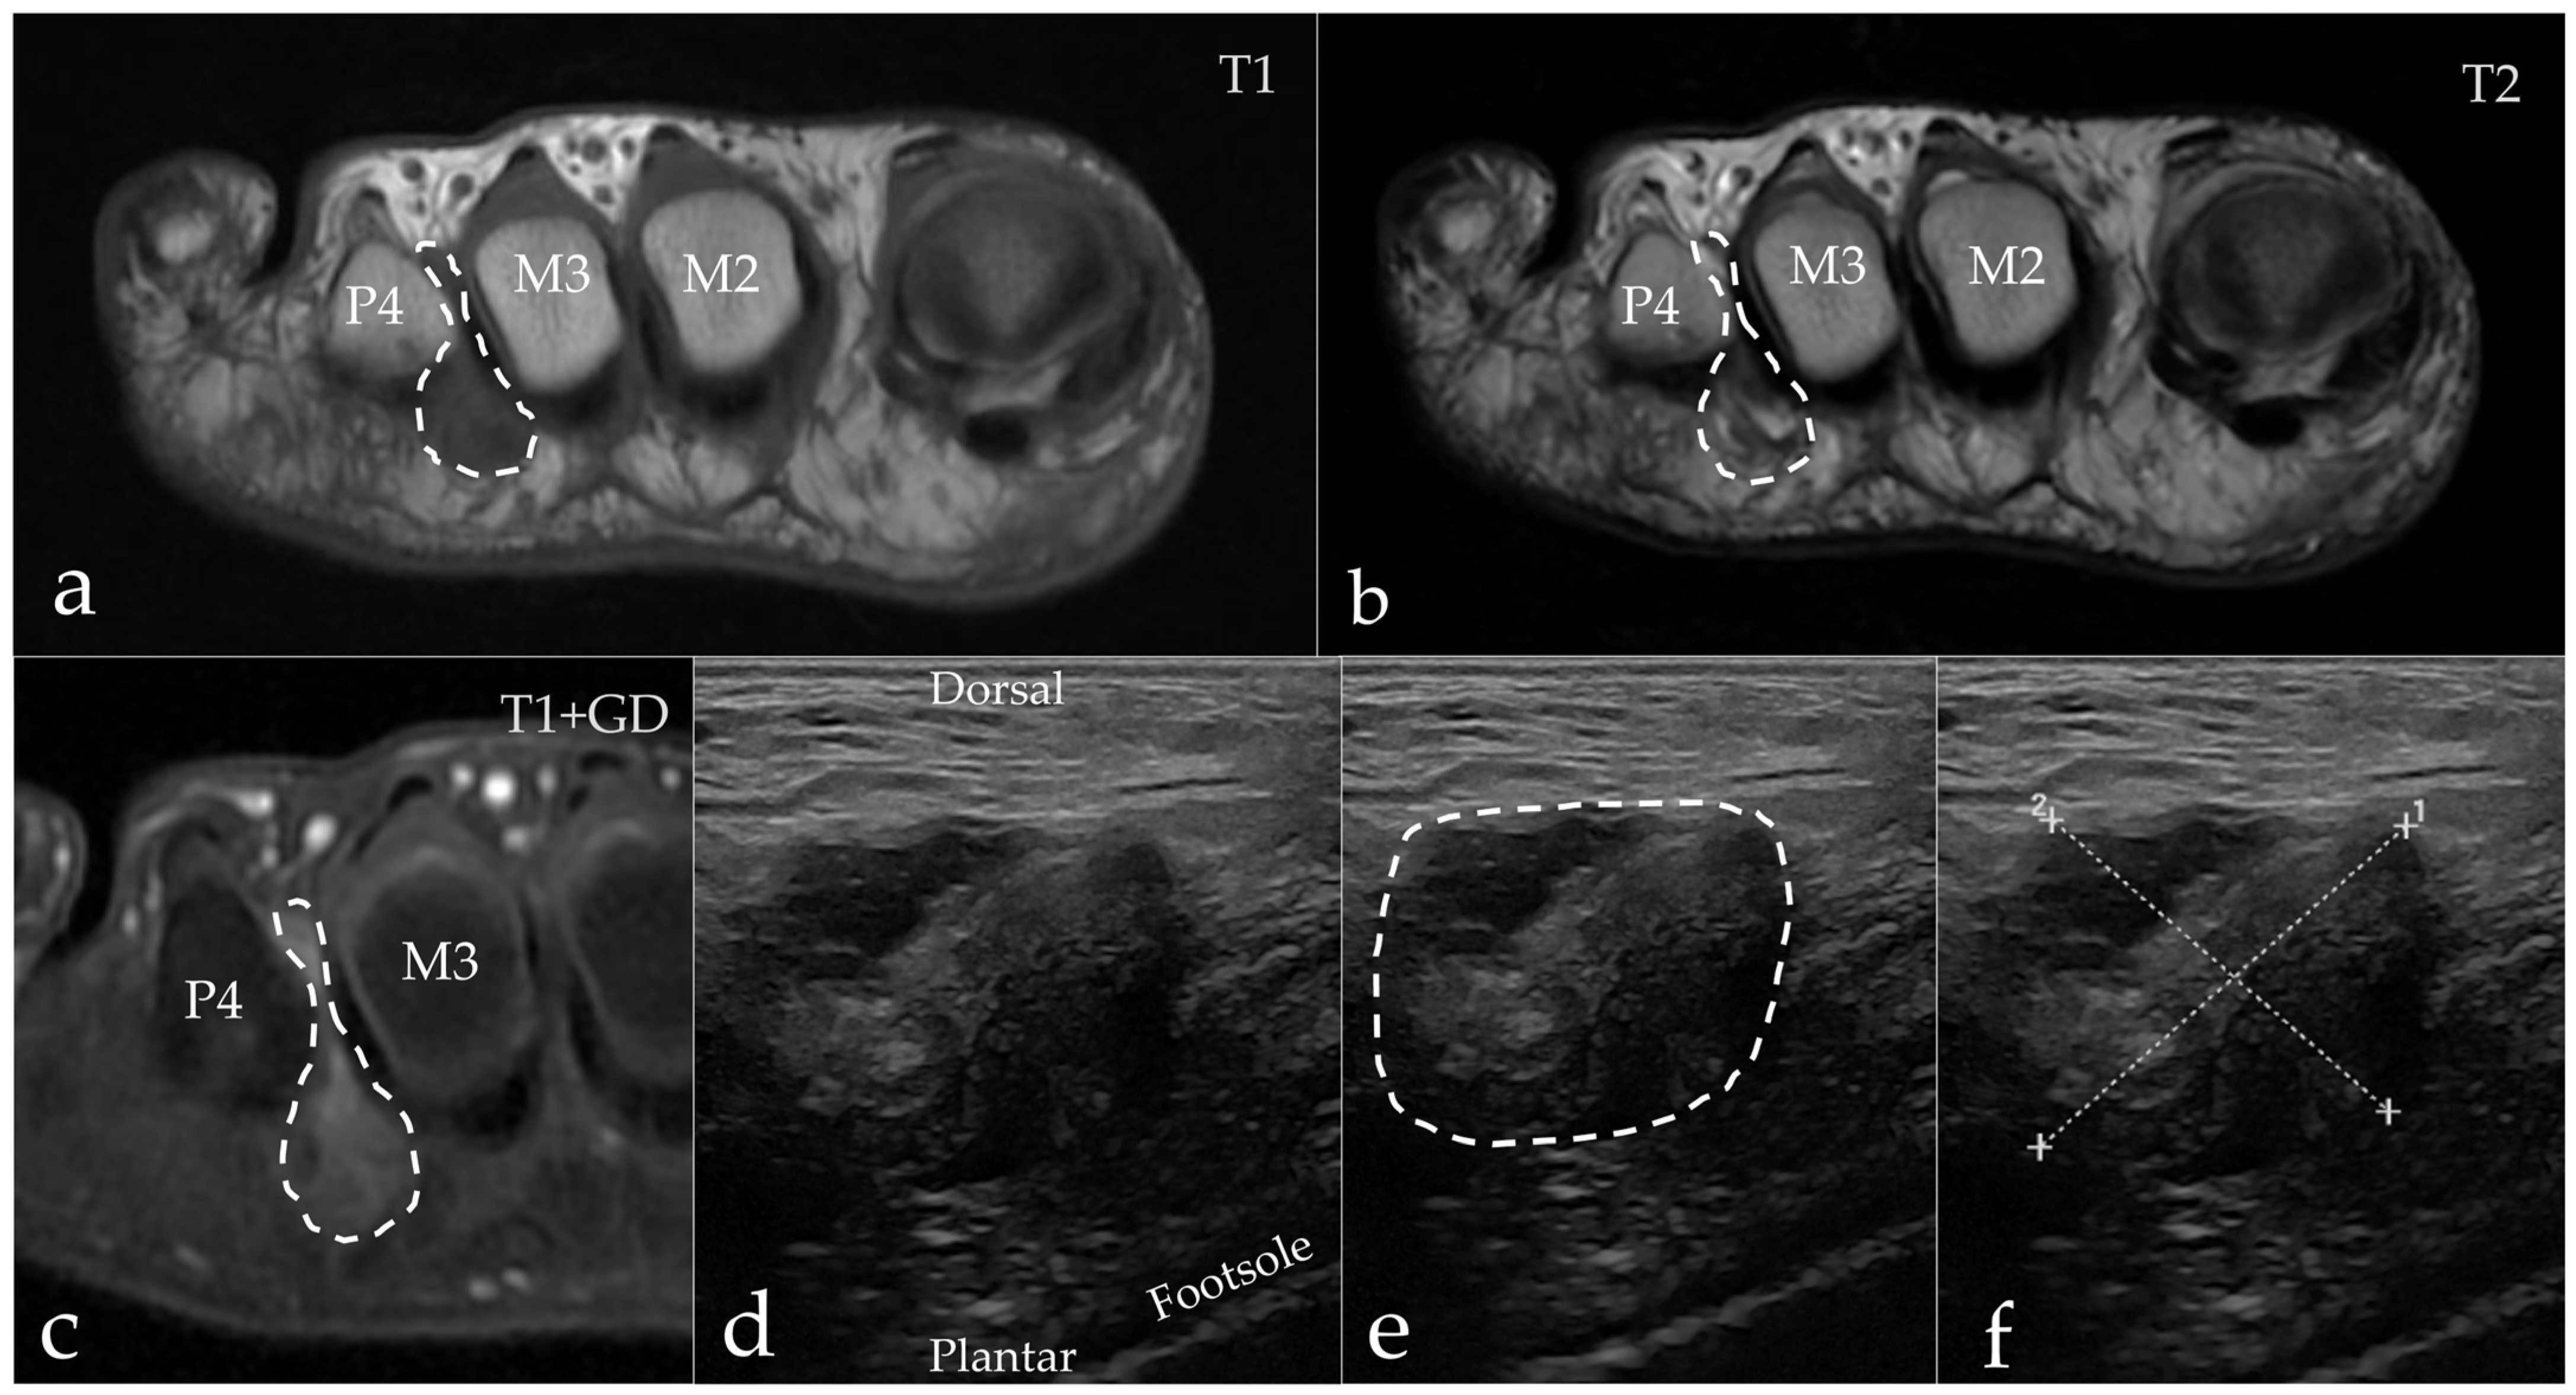

3.2. Imaging Results